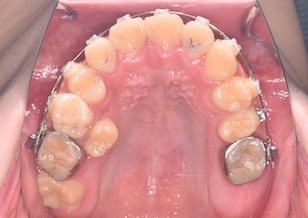

BeforeⅢは、右上顎第2大臼歯が萌出開始しています。左上の乳歯が脱落し、左上顎第2小臼歯にマルチブラケット装置を装着して牽引中のお写真です。

AfterⅢは、右上の乳臼歯を抜歯し、右上顎第2小臼歯にマルチブラケット装置を装着して牽引中のお写真です。